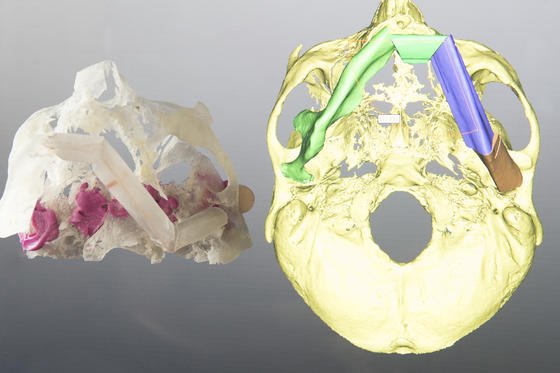

In der Klinik für Mund-, Kiefer- und Gesichtschirurgie (MKG) der Universitätsmedizin Mainz entstehen individuelle dreidimensionale Patientenmodelle aus dem eigenen 3D-Drucker, die selbst kleinste anatomische Strukturen wie fein verästeltes Knochengewebe abbilden. Anhand dieser Modelle können die Mediziner beispielsweise durch Tumorleiden bedingte Kiefer-, Kopf- oder Gesichtsrekonstruktionen operativ besser planen und Transplantate präziser anpassen.

Sei es Nase oder Stirn – der neue 3D-Drucker der Klinik für Mund-, Kiefer- und Gesichtschirurgie (MKG) an der Johannes Gutenberg-Universität kann alles exakt nachbilden. Selbst kleinste Details wie fein verästeltes Knochengewebe bekommt diese Technik hin. Mit solchen maßgetreuen Schablonen können Chirurgen Patienten körpereigene Transplantate passgerechter einsetzen. In Mainz sieht man das als enormen Schritt hin zu einer immer stärker individualisierten Medizin. Die dreidimensionalen Modelle werden im Maßstab 1:1 gefertigt. Die Vorab-Informationen dazu liefern Bildgebungsverfahren wie Computertomographie, Röntgen oder MRT.

Das 3D-Verfahren hat etliche Vorteile: Anhand der Modelle können Mediziner eine bevorstehende Operation gedanklich durchspielen, bevor es ernst wird. Um es zu verdeutlichen: Eine Lücke im Kiefer muss geschlossen werden, dafür soll ein Stück des Wadenbeins entfernt und anschließend an anderer Stelle wieder eingesetzt werden. Zuerst erstellt der 3D-Drucker ein Modell des Kiefers und des Wadenbeins.

Der Mediziner plant dann die OP am lebensechten Modell und probt sie sogar in Grundzügen. Derart vorbereitet kann er bei der realen OP das Knochenstück aus dem Wadenbein so präzise herausnehmen, dass es passt punktgenau in den defekten hineinpasst. Das ist eine schonende Methode, die weniger Folgeschäden für das Wadenbein hat als eine herkömmliche OP.